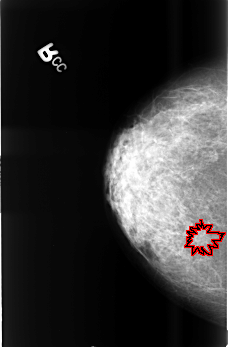

B_3399_1.RIGHT_MLO

RIGHT_MLO LINES 4552 PIXELS_PER_LINE 2928 BITS_PER_PIXEL 12 RESOLUTION 50 OVERLAY

FILE: B_3399_1.RIGHT_MLO.OVERLAY

TOTAL_ABNORMALITIES 1

ABNORMALITY 1

LESION_TYPE CALCIFICATION TYPE PUNCTATE DISTRIBUTION CLUSTERED

LESION_TYPE MASS SHAPE IRREGULAR-ARCHITECTURAL_DISTORTION MARGINS SPICULATED

ASSESSMENT 5

SUBTLETY 3

PATHOLOGY MALIGNANT

TOTAL_OUTLINES 1

BOUNDARY